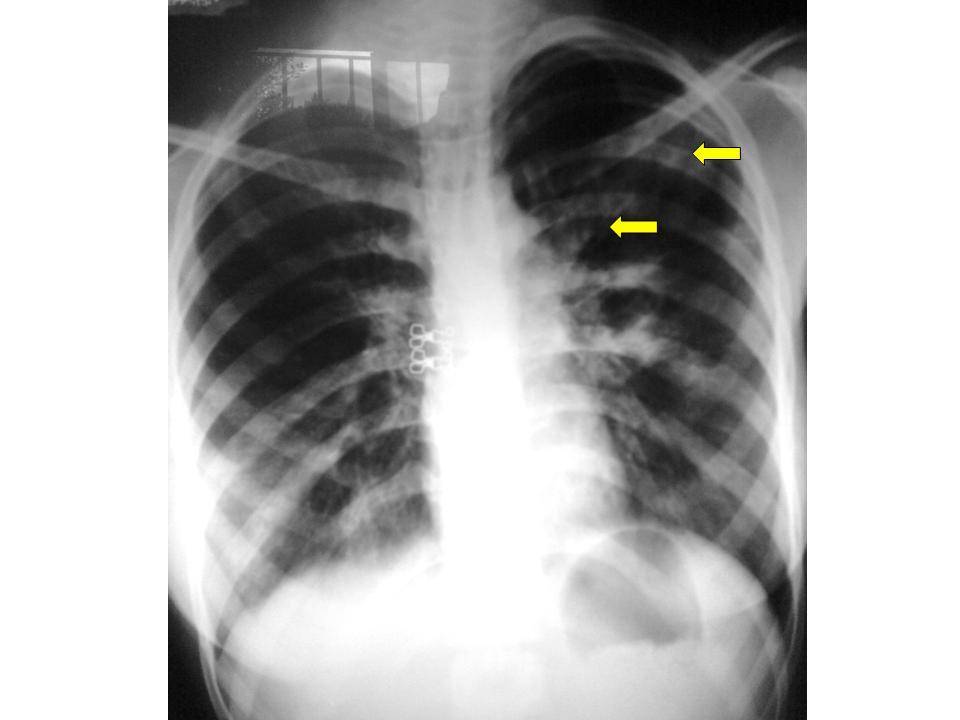

Рентгенодиагностика бронхопневмонии: Советы и примеры

Раздел: Альбом открытий